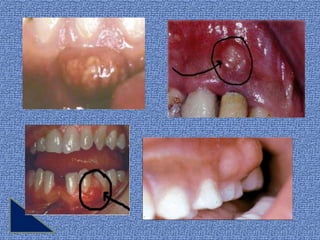

El síntoma más prominente es la presencia de

una ELEVACIÓN OVOIDE de la encía a lo largo

de la cara lateral de la raíz.

Los A.P. ubicados en la profundidad del

periodonto se identifican con menos facilidad

por la tumefacción. Otra observación es la

SUPURACIÓN, ya sea de una fístula o de una

B.P. puede ser :

Los síntomas clínicos pueden incluir:

Sensibilidad

dolor                            tumefacción

de la encía

Aumento de

elevación

movilidad